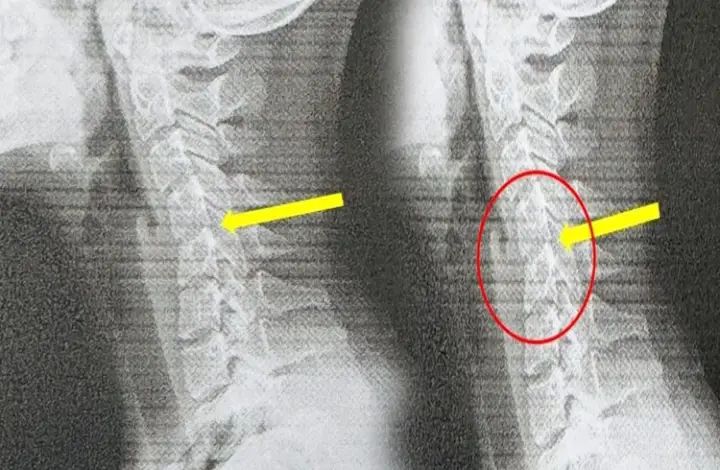

ಜೊತೆಗೆ ಅವಳ ಕುತ್ತಿಗೆ ಬಾಗುತ್ತಿತ್ತು. ವೈದ್ಯರು ತುರ್ತಾಗಿ ಸಿಟಿ ಸ್ಕ್ಯಾನ್ ಮಾಡಿದಾಗ. ಅದು ಆಘಾತಕಾರಿ ಸಂಗತಿಯನ್ನು ಬಹಿರಂಗಪಡಿಸಿತು.

ಅವಳ ಗರ್ಭಕಂಠದ ಬೆನ್ನುಮೂಳೆಯು ತನ್ನ ನೈಸರ್ಗಿಕ ಆಕಾರವನ್ನು ಕಳೆದುಕೊಂಡಿತ್ತು. ಮತ್ತು ಕೆಲವು ಪ್ರದೇಶಗಳಲ್ಲಿ ಕಶೇರುಖಂಡಗಳು ಜಾರಿಬೀಳುವ ಲಕ್ಷಣಗಳನ್ನು ಸಹ ವೈದ್ಯರು ಕಂಡುಕೊಂಡರು.

‘ಟೆಕ್ಸ್ಟ್ ನೆಕ್’ ಎಂದು ಕರೆಯಲ್ಪಡುವ ಅವಳ ಸ್ಥಿತಿಯು ಅಕಾಲಿಕ ಗರ್ಭಕಂಠದ ಕ್ಷೀಣತೆಯ ಮುಂಚಿನ ಎಚ್ಚರಿಕೆ ಸಂಕೇತವಾಗಿದೆ ಎಂದು ಅವರು ಹೇಳಿದರು. ಇದರ ಬಗ್ಗೆ ಮಾತನಾಡುತ್ತಾ, ತೈವಾನೀಸ್ ವೈದ್ಯರು ಅವಳ ಸ್ಥಿತಿ. ಇಂದಿನ ಯುವಜನತೆ ಎದುರಿಸುತ್ತಿರುವ ಸಮಸ್ಯೆಯಾಗಿದೆ. ‘ಅವರು ಪ್ರತಿದಿನ ಗಂಟೆಗಟ್ಟಲೆ ತಮ್ಮ ಫೋನ್ಗಳನ್ನು ನೋಡುತ್ತಾ, ಕಾರ್ಯಕ್ರಮಗಳನ್ನು ನೋಡುತ್ತಾ ಮತ್ತು ಆಟಗಳನ್ನು ಆಡುತ್ತಾ ಕಳೆಯುತ್ತಾರೆ. ಆದರೆ ಅವರ ದೇಹವು ನೋವಿನಿಂದ ಕಿರುಚುವವರೆಗೂ, ಅವರಿಗೆ ಸಮಸ್ಯೆಯ ತೀವ್ರತೆಯ ಅರಿವಿರಲಿಲ್ಲ.’ ಅವರು ಹೇಳಿದರು.